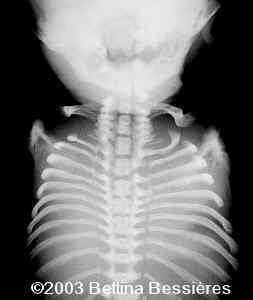

Abnormal vertebrae.

case0093-17

The radiohumeral fusion, and abnormal vertebrae:

case0093-08

case0093-09